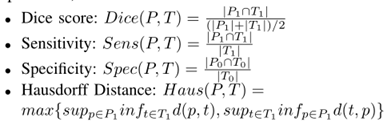

评估指标:分割精度分别通过Dice评分、灵敏度、特异性和Hausdorff95距离来衡量。

其中P代表模型预测,T代表地面真实标注。t1和t0是预测为肿瘤区域的阳性和阴性的子集体素。对P1和P0也进行了类似的设置。此外,Hausdorff95在将模型预测与地面真实分割进行比较时测量距离。sup代表上确界,inf代表下确界。对于每个度量,分别评估三个区域,即增强肿瘤(ET,标记1)、全肿瘤(WT,标记1、2和4)和肿瘤核心(TC,标记1和4)。